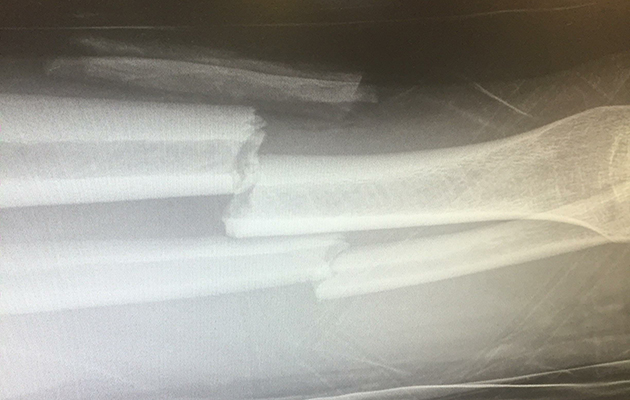

Ryann was helped off her horse and taken to hospital by ambulance. Scans revealed she had broken her tibia and fibula and required an operation to insert a pin to secure the break.

She later went in for a second operation during which a pin was inserted from her knee to her ankle.